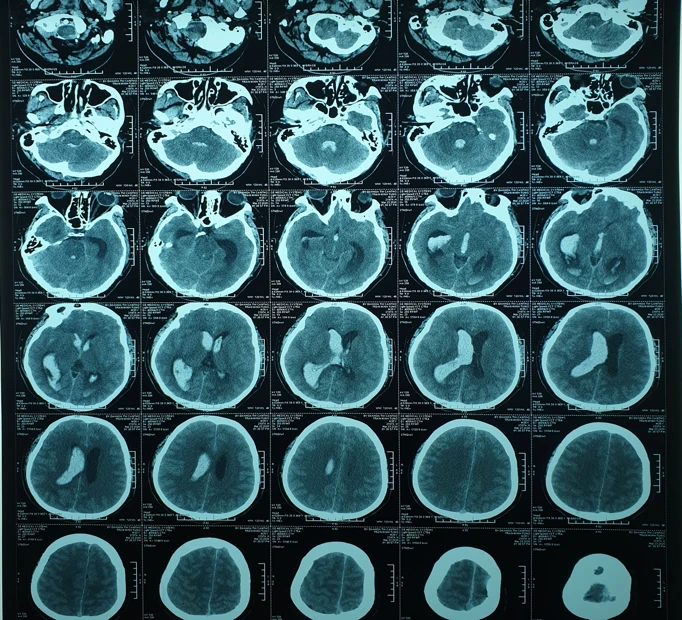

Hình ảnh chụp CLVT sọ não trước và sau mổ. Ảnh: HẢI DƯƠNG 1 Hình ảnh chụp CLVT sọ não trước và sau mổ. Ảnh: HẢI DƯƠNG 2

Hình ảnh chụp CLVT sọ não trước và sau mổ.

Kết quả chụp cắt lớp vi tính (CLVT) sọ não cho thấy có tình trạng chảy máu não tràn vào hệ thống não thất, gây giãn toàn bộ hệ thống não thất, nguy cơ tử vong gần như hoàn toàn nếu không xử trí kịp thời.

Kết quả CLVT sọ não kiểm tra sau mổ cho thấy hệ thống não thất đã bớt giãn nhưng vẫn còn tụ máu nhiều, khả năng tắc ống dẫn lưu là rất cao. Lúc này, êkíp tiếp tục bơm thuốc tiêu sợi huyết vào não thất thông qua ống dẫn lưu kết hợp theo dõi áp lực nội sọ liên tục.

Kết quả CLVT tuần thứ nhất sau mổ tốt ngoài mong đợi, máu tụ trong não thất giảm đáng kể, bệnh nhân tri giác cải thiện, giảm sốt và đã được rút ống dẫn lưu não thất.